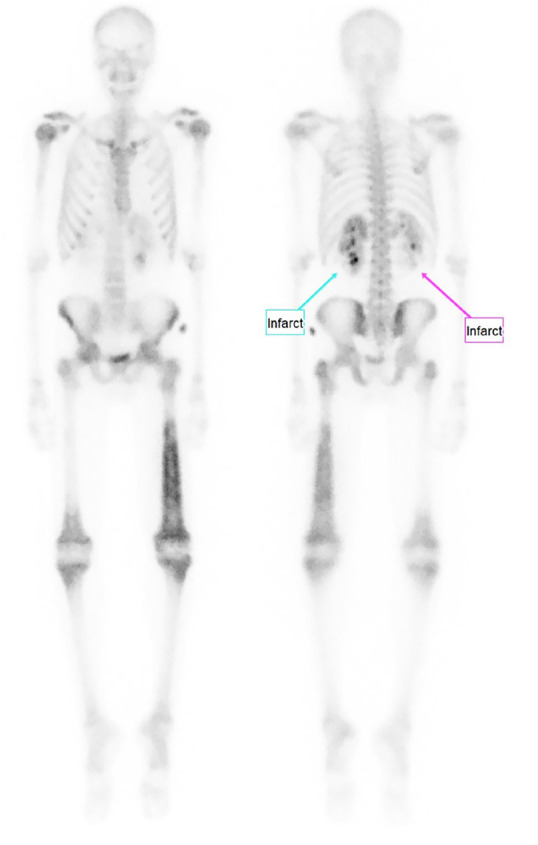

Although extrapulmonary Coccidioides infection is rare, it has been shown to disseminate to the skin and musculoskeletal system, with a strong affinity for bone. We present a case of disseminated Coccidioides infection with bone scintigraphy indicating diffuse fungemia despite equivocal serum assay, leading to appropriate antifungal therapy and a full recovery.